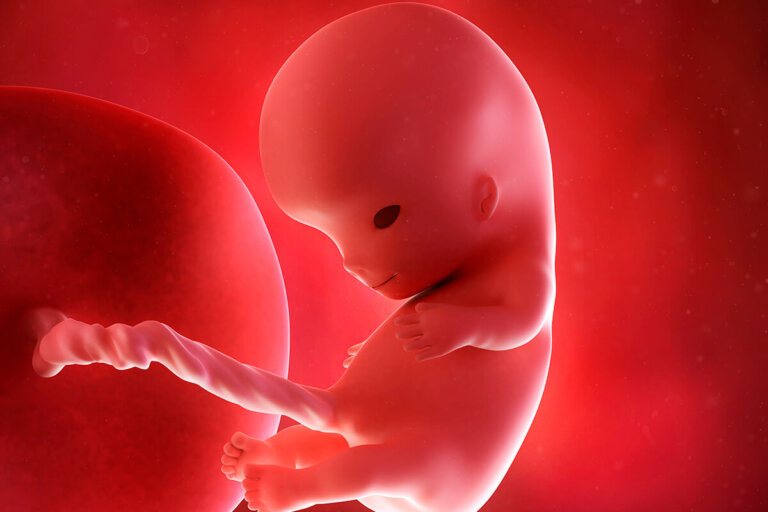

¡Felicidades! Tu bebé está alcanzando los 2 centímetros. La semana 9 del embarazo marca el inicio del final de la etapa embrionaria. La “colita” de la médula espinal casi ni se percibe. El embrión va fortaleciéndose y tomando una apariencia más parecida a lo que conocemos, a pesar de su diminuto tamaño.

Nos acercamos al final de la etapa como embrión que, en términos científicos, marca que los órganos de base están formados. Ahora inicia la definición y el aumento de su tamaño para adquirir funciones. En pocos días nos referiremos al bebé como feto.

El bebé ha pasado a medir alrededor de 1 pulgada de largo, con un peso de 0,07 onzas, apenas 2 gramos. Diríamos que es como una aceituna verde mediana. A pesar de su diminuto tamaño, la cabeza está un poco más redondeada y enderezada. También se han desarrollado más el cerebro, las orejas (que ya cuentan con lóbulos) y la nariz (que tiene un pequeño bulto).

También tiene la boca por completo formada, lo que generará que el bebé empiece a moverla involuntariamente, cerrándola y abriéndola. Esto cambiará en las siguientes semanas, durante las que el cerebro desarrollará las conexiones con los músculos; de esta forma, podrá generar estímulos para que haya movimientos voluntarios. O sea, tu bebé comenzará decidir cuando abrir o cerrar su cavidad bucal.

Además, los dedos de los pies y los órganos esenciales del bebé, como el corazón, el cerebro, los riñones, el hígado y los pulmones, comienzan a distinguirse mejor.